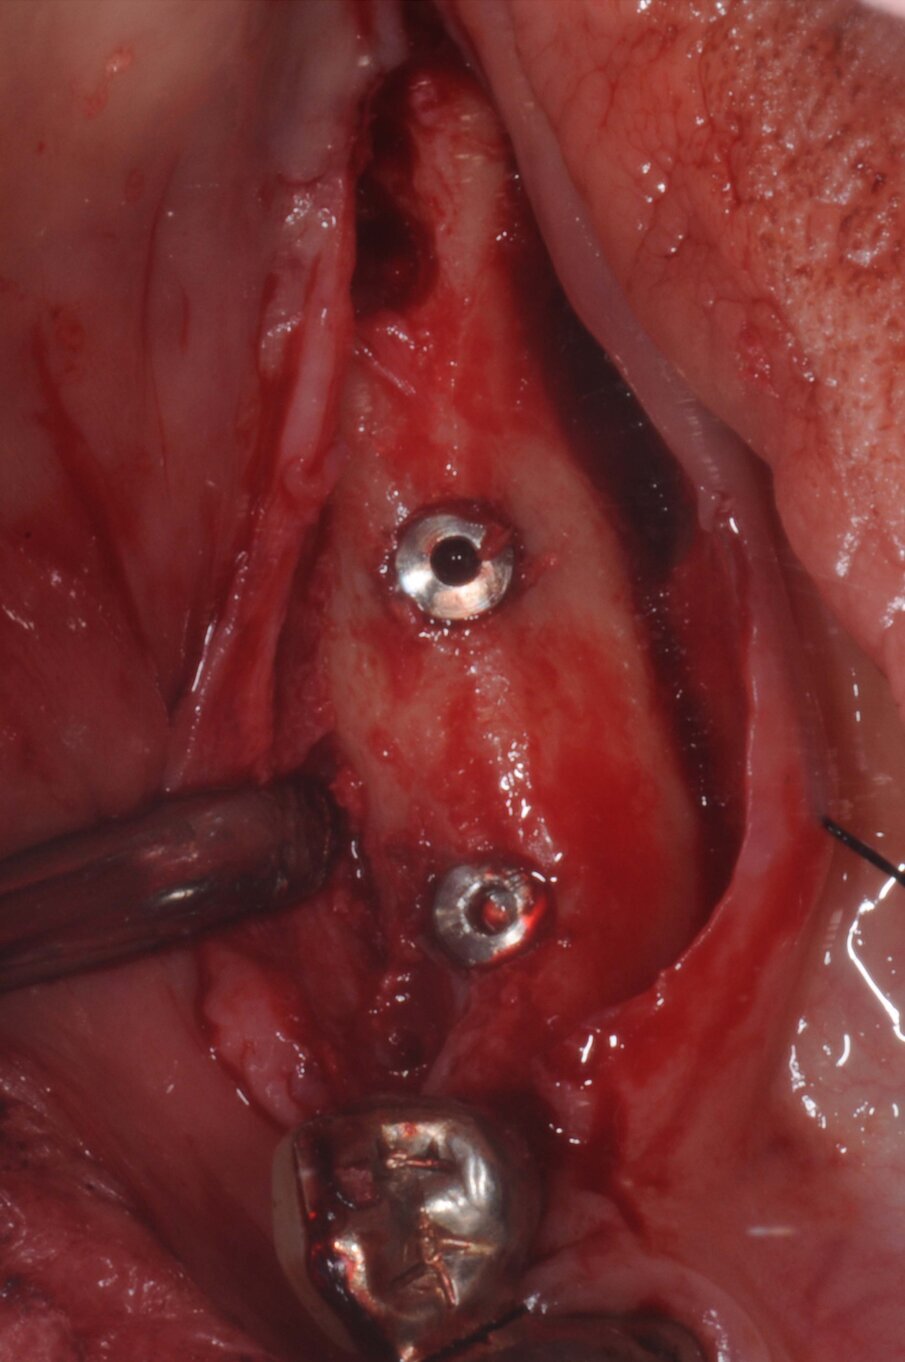

La terapia anticoagulante non è stata interrotta prima della chirurgia ed è stata somministrata la profilassi antibiotica come da protocollo. È stata eseguita un’incisione crestale senza tagli di scarico che è stata estese distalmente fino al trigono retromolare per esporre la branca mandibolare ed avere un sito per raccogliere osso autologo con una fresa carotatrice. Sono state eseguite le osteotomie a basso numero di giri come da protocollo BTI per ottenere un’ulteriore quantità di osso autologo raccolto dalle frese e inseriti due impianti BTI Core 3,75 x 4,5 e 3,5 x 6,5 rispettivamente in posizione 46 e 45.

L’osso autologo è stato mescolato con gel piastrino ottenuto da centrifugazione del sangue del paziente mediante metodica Endoret BTI. La membrana ottenuta è stata applicata a protezione della corticale vestibolare. Ulteriori membrane di gel piastrino sono state applicate sopra l’osso autologo. La stabilita primaria di entrambi gli impianti era superiore ai 50 Newton per cui sono stati avvitati i pilastri Multi-Im e i pilastri di guarigione per un tecnica con una sola chirurgia. Sono state applicate suture sintetiche non riassorbibili a punti staccati (Figg. 3–10). Successivamente è stata eseguita una Rx di controllo. Le suture sono state rimosse a due settimane e la paziente riferì di avere avuto disagi minimi, senza ematomi o edemi estesi e scarsa dolenzia che non richiese l’assunzione di antinfiammatori.